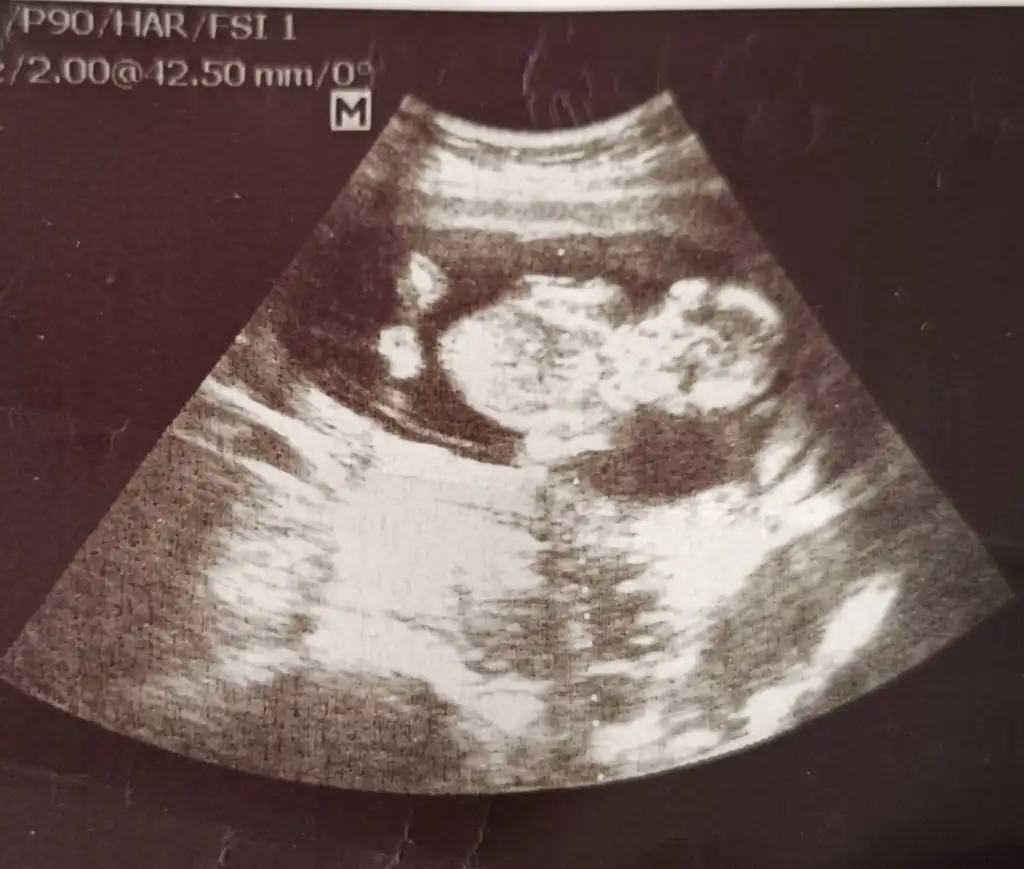

IMG_20240402_023703.webp

Burda usg olarak 14 haftalıkdı

Hayalet gibi çıkmış ama🤭😂